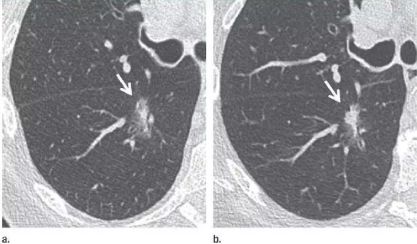

在中国人的印象里 心和肺一直是“形影不离”的 海尔兄弟 成语里有 撕心裂肺 狼心狗肺 没心没肺 …… 医学术语里有 心肺功能 心肺复苏 心肺康复 …… 尤其是当肺部查出“小阴影” 心更是脱不了关系 每天都惴惴不安 今天肿医君就来带大家看看 这让人烦恼的 肺部结节 Part.1: 肺部结节 真实病例: 张阿姨今年48岁,单位体检结果显示,肺上有一个0.8cm的小结节。张阿姨听说肺结节会变成肺癌,她担心极了,让儿子帮忙上网查询,向其他人咨询,可她得到的建议多种多样,让刘阿姨无所适从。 慢慢长大会不会变成肺癌啊 肺癌是世界上发病率及死亡率最高的恶性肿瘤,也是我国发病率和死亡率最高的疾病。目前约 75% 的肺癌患者在诊断时已属晚期,5年生存率仅为 15.6%。提高肺癌生存率的唯一途径是端口前移,早发现、早诊断和早治疗。 美国《化学文摘》2018全球癌症统计报告显示 肺癌(蓝色)高居发病率和死亡率之首 全球发病率11.6% 全球死亡率18.4% 湖南省肿瘤医院胸外一科 主任医师 陈跃军 很多患者忧心忡忡,不知道是否该进行进一步检查。如果对体检报告中的一些疾病迹象置若罔闻,等“小结节”长大变成了“肿块”,往往已错过最佳手术时机。那么我们应该怎么正确对待肺部结节呢? Part.2: 结节的分类 知识点 肺部结节(solitary pulmonary nodule,简称SPN)是肺实质完全包围的单发小病灶,类圆形或不规则形状,通常边界清晰,由肺实质包裹,不累及肺门和胸腔纵隔胸膜,不引发肺炎、肺不张或胸腔积液的组织。 肺结节分类如下 按大小: 肺结节中,直径1cm以内的称为小结节,直径0.5cm以内为微结节。局部病灶直径>3cm者称为肺肿块,也有医院将其报告为肺肿物或肺占位。 肺部结节尺寸越大,肺癌的可能性相对较大。 按数量: 肺结节可以是孤立性或多发性,孤立性肺结节即单个病灶,多无明显症状,属于边界清楚、密度增高且周围被含气肺组织包绕的软组织影。2个及以上病灶称为多发性肺结节。 肺结节的个数与肺癌可能性没有相关性 按密度: 根据病灶密度不同,肺结节还可分为实性肺结节和亚实性(非实性)肺结节,后者包括纯磨玻璃样结节。实性肺结节是肺内局限的密度增高影,病变密度相对较高,掩盖其中走行的肺细小支气管影和血管影(肺纹理);纯磨玻璃结节指CT显示的肺内密度稍增高影,通过病灶仍然能看到肺纹理影,就像透过磨玻璃观察到相对模糊的影像一样。 磨玻璃样结节尤其是持续存在的磨玻璃样结节,一般是肿瘤性病变 湖南省肿瘤医院胸外一科 主任医师 陈跃军 发现肺结节之后,不用过分紧张,但也不能掉以轻心,大部分肺结节都是良性的,只有少数肺结节是恶性的。 Part.3: 区分结节性质 结节良性的三大表现 1、 结构清晰,边缘平滑。内含脂肪和钙化的实性结节(箭头),符合错构瘤表现。建议进一步 CT 随访。 源自美国Fleischner 学会2017 年公布案例图(下同) 2、 有明显钙化痕迹。CT 图像显示边界清楚的中心钙化(a)或层状钙化(b)结节,均为典型的肉芽肿表现。建议进一步 CT 随访。 3、没有变大的趋势,甚至逐渐消失。(a)左肺上叶层厚 1 mm 的 CT 横断面图像,显示一个模糊的 10 mm 大小磨玻璃样结节(箭头)。(b)4 个月后的 CT 随访图像,显示未经治疗的病变在随访间期消失,符合良性病因,如局灶性感染。 结节恶性的三大表现 1、 毛刺状结节 左肺上叶层厚 1 mm 的 CT 横断面图像,显示一个可疑的实性毛刺状结节(箭头)。手术证实为浸润性腺癌。 2、 磨玻璃区域逐渐长大的结节 (a)右肺中部层厚 1 mm 的 CT 横断面图像,显示一个 10 mm 大小的纯磨玻璃样结节(箭头)。(b)同一位置 15 个月后的 CT 随访图像,显示病变的不透明度只有很小增加。(c)取得 b 图 10 个月后,同一位置的 CT 图像,显示结节已发展成较大的实性结节。手术切除证实为 1A 期浸润性鳞屑样为主的腺癌 3、实性结节逐渐变大的结节 (a)右肺下叶上段层厚 1 mm 的 CT 横断面图像,显示一个高度可疑(较大、磨玻璃样外观和实性形态)的部分实性结节(箭头)。(b)3 个月后的 CT 随访图像显示,实性成分的大小逐渐增加。手术显示为浸润性腺癌。 除了上述影像资料,咨询者的生活方式也是判断依据。 肺癌的高危人群 (1)年龄在55岁以上; (2)年数乘以每天吸烟的支数>400支*年的吸烟患者,其中也包括曾经吸烟,但戒烟时间不足15年者;被动吸烟者; (3)有职业暴露史(石棉、铍、铀、氡等接触者); (4)有恶性肿瘤病史或肺癌家族史; (5)有慢性阻塞性肺疾病(COPD)或弥漫性肺纤维化病史。 Part.4: 发现结节怎么做? 1、肺部小结节并不等于肺癌,并且大部分是良性的,有的通过保守治疗如抗炎或抗痨治疗,甚至不做任何治疗观察后消失。因为人体有自身免疫力的,只要营养好,一般的炎性病变可自行吸收。 2、当医生判断结节恶性可能性较小时,还是建议患者要定期检查胸部CT。5毫米以下的微结节每年复查一次,5至10毫米的小结节每三个月复查一次,随访三至五年。 CT在肺内病变中的诊断优势非常明显,CT通过显示组织横断面及三维结构图像进行诊查,有效避免了肺与心脏、纵隔、横膈等组织的重叠,能发现肺尖、脊柱旁、靠近胸膜、心脏后方等部位胸片难以发现的病灶。另外,低剂量CT筛查所产生的射线剂量很低,对人体的影响极低。 3、当医生判断为恶性可能性较大时,应早期进行手术(胸腔镜)治疗。国内外多个研究结果显示,经过手术治疗的I期患者的10年生存率达到了90%以上。 目前微创胸腔镜手术是治疗肺部小结节、早期肺癌的主要方法。胸腔镜手术应用广泛,只需一个1cm胸腔镜观察孔和一个2-3cm操作孔,行肺叶或肺段切除术,疗效明确,创伤非常小,疼痛轻,术后恢复快,不需要做任何的化疗和放疗。 在我们临床工作中对上千例磨玻璃结节、微小结节患者的长期临床观察研究结果显示,90%以上患者的结节没有发生变化,10%的患者在随访过程中发现结节长大或实质成分增加等改变,及时手术,但没有一例出现复发转移,所以只要找对了专家,定期随访,并不会耽误治疗。 最危险的情况其实是病人发现肺部结节去看医生,医生考虑肺部小结节可暂时不处理,建议定期复查,而病人把不手术、不服药误认为没病,一直拖到出现症状后再去就诊,耽误了病情。